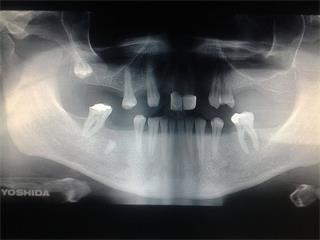

Je toho nesmierne veľa. Dodnes sa snaží zobrať aj nejaké brigády,no vieme,že veľmi trpí.Moja sestra je tiež veľmi chorá,na jej liečbu ide veľa peňazí.Mamička pracuje ,no jej príjem stačí na bežné účty.Chcela by som prejaviť svoju vďaku človeku,ktorý ma vychoval,no moje možnosti sú malé.Môj OTEC,OTECKO,OCINKO a ešte neviem ako by som ho mohla ospevovať má v zlom stave svoj chrup.Strašne by som mu chcela dopriať,aby si ich mohol dať urobiť.Stále hovorí,že peniažky treba na liečbu mojej sestry.Ja viem,že on myslí stále len na rodinu,aby sa mali oni dobre.Ale tak veľmi by si to zaslúžil.Prosím Vás ľudia pomôžte mi spraviť svojho milovaného OTECKA šťastnejším.Toľko toho mi dal do života,hoci som jeho nevlastná dcéra.Pamätám jeho čierne brčkavé vlasy toho čudáka : )) ,dnes má už len šediny a bolesti.No napriek všetkému jeho srdiečko je stále dobré .A jeho náruč otvorená aj keď som nevlastná dcéra.ĎAKUJEM TI OCI !!!

PROSÍM VÁS O POMOC aby za jeho úsmevom nebola bolesť.